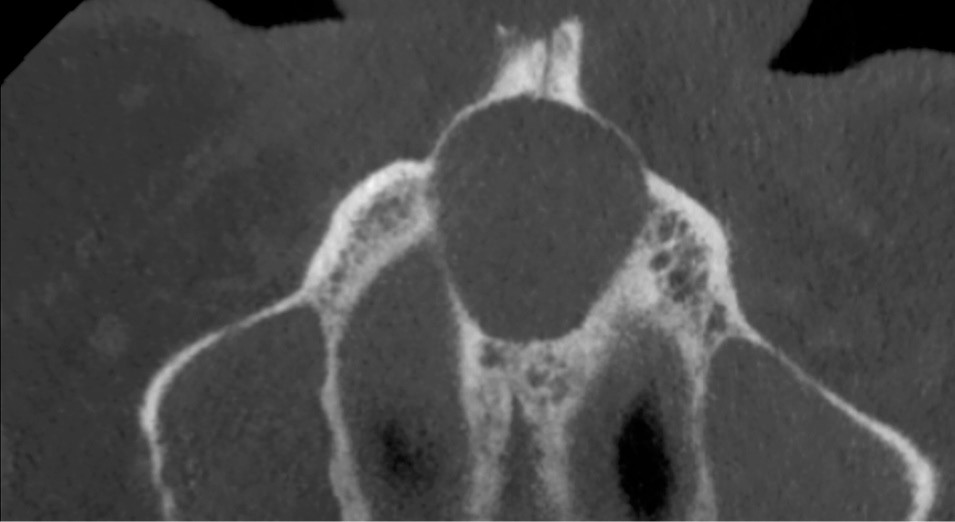

- Centré sur la ligne médiane de la portion antérieure du palais.

- Lésion ostéolytique radio-claire.

- Homogène et bien délimitée.

- Uni-loculaire (fig. 3), pouvant présenter un aspect caractéristique de « cœur de carte à jouer ».

- Diamètre moyen des lésions de 2 cm.